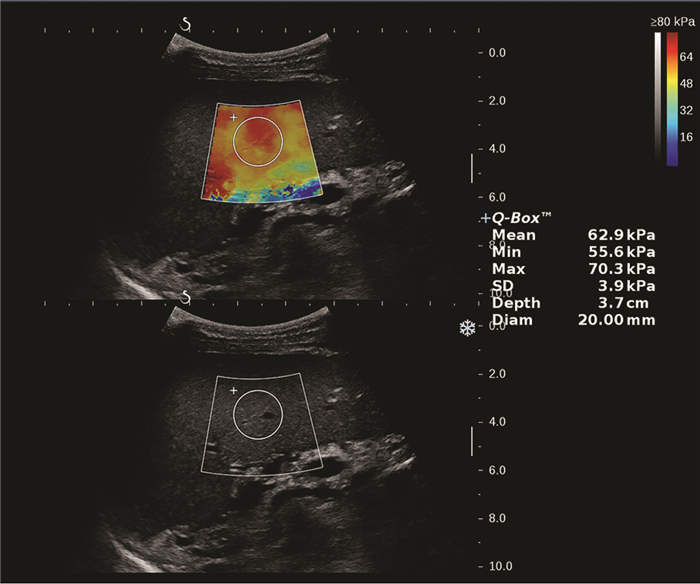

Clinical value of two-dimensional shear wave elastography in predicting esophageal varices in patients with hepatitis B cirrhosis by evaluating liver and spleen stiffness

Xuemei WANG, Yao ZHANG, Xueping YANG, Yue WANG, Mixue WANG

2021, 37(5): 1081-1084. DOI: 10.3969/j.issn.1001-5256.2021.05.021

Abstract(1416) HTML (293) PDF (2305KB)(79)

Abstract:

Objective  To investigate the value of two-dimensional shear wave elastography (2D-SWE) in the noninvasive evaluation of the presence or absence of esophageal varices (EV) in patients with hepatitis B cirrhosis by liver stiffness measurement (LSM) and spleen stiffness measurement (SSM).  Methods  A total of 172 patients who were diagnosed with hepatitis B cirrhosis in Beijing Ditan Hospital, Capital Medical University, from April 2019 to February 2020 were enrolled in a prospective study, and according to the results of gastroscopy, they were divided into non-EV group and EV group. The two groups were compared in terms of spleen thickness (ST), spleen diameter (SD), LSM, and SSM. The independent samples t-test was used for comparison of normally distributed continuous data between two groups, and the Mann-Whitney U test was used for comparison of non-normally distributed continuous data between two groups; the chi-square test was used for comparison of categorical data. The receiver operating characteristic (ROC) curve was used to investigate the value of LSM and SSM in the diagnosis of EV, and the Z test was used to compare the diagnostic accuracy of LSM and SSM.  Results  There were 121 patients in the EV group and 51 patients in the non-EV group. There were significant differences between the two groups in ST (t=8.143, P < 0.001), SD (t=7.363, P < 0.001), LSM (Z=3.024, P=0.002), SSM (t=15.142, P < 0.001), and presence or absence of ascites (χ2=22.101, P < 0.001). LSM had an area under the ROC curve (AUC) of 0.646 (95% confidence interval [CI]: 0.570-0.718) in the diagnosis of EV, with a sensitivity (Se) of 83.47%, a specificity (Sp) of 47.06%, a positive predictive value (PPV) of 78.9%, and a negative predictive value (NPV) of 54.5% at the optimal cut-off value of 13.16. SSM had an AUC of 0.951 (95% CI: 0.907-0.978) in the diagnosis of EV, with an Se of 80.99%, an Sp of 96.08%, a PPV of 98.0%, and an NPV of 68.1% at the optimal cut-off value of 38.08. SSM had a better diagnostic accuracy than LSM (Z=6.096, P < 0.001).  Conclusion  LSM and SSM can be used to predict the presence or absence of EV in patients with hepatitis B cirrhosis. SSM has a higher accuracy than LSM and can provide accurate diagnostic information for clinical practice.